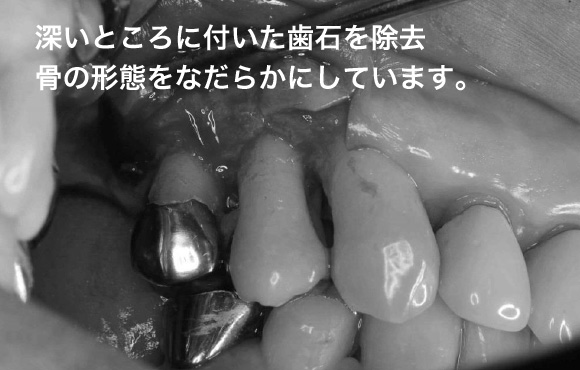

■骨を滑らかにする。プラークコントロールをしやすい環境を作る。

■道路の側溝は汚れがいっぱい、歯周病でできた骨のがたがたを放置しておくとばい菌で一杯になり、歯周病が再発します。

■歯周病は歯茎に隠れた骨の病気なのです。

■歯周外科手術でなるべく骨をなだらかしてお掃除のしやすい形態に変えていきます。

歯肉弁剥離掻把術

骨に大きな段差がある場合は

骨に大きな段差がある、骨をなだらかにするには限界があります。